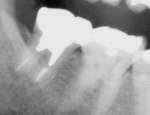

抜髄根管治療症例(2) 女性Kさま

H16.04.26

治療前

H16.05.21

根充後

H18.06.17

治療後2年